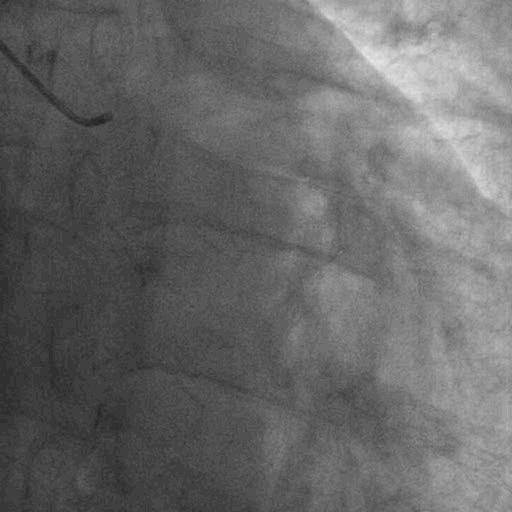

左冠造影:

右冠造影:

双侧造影: